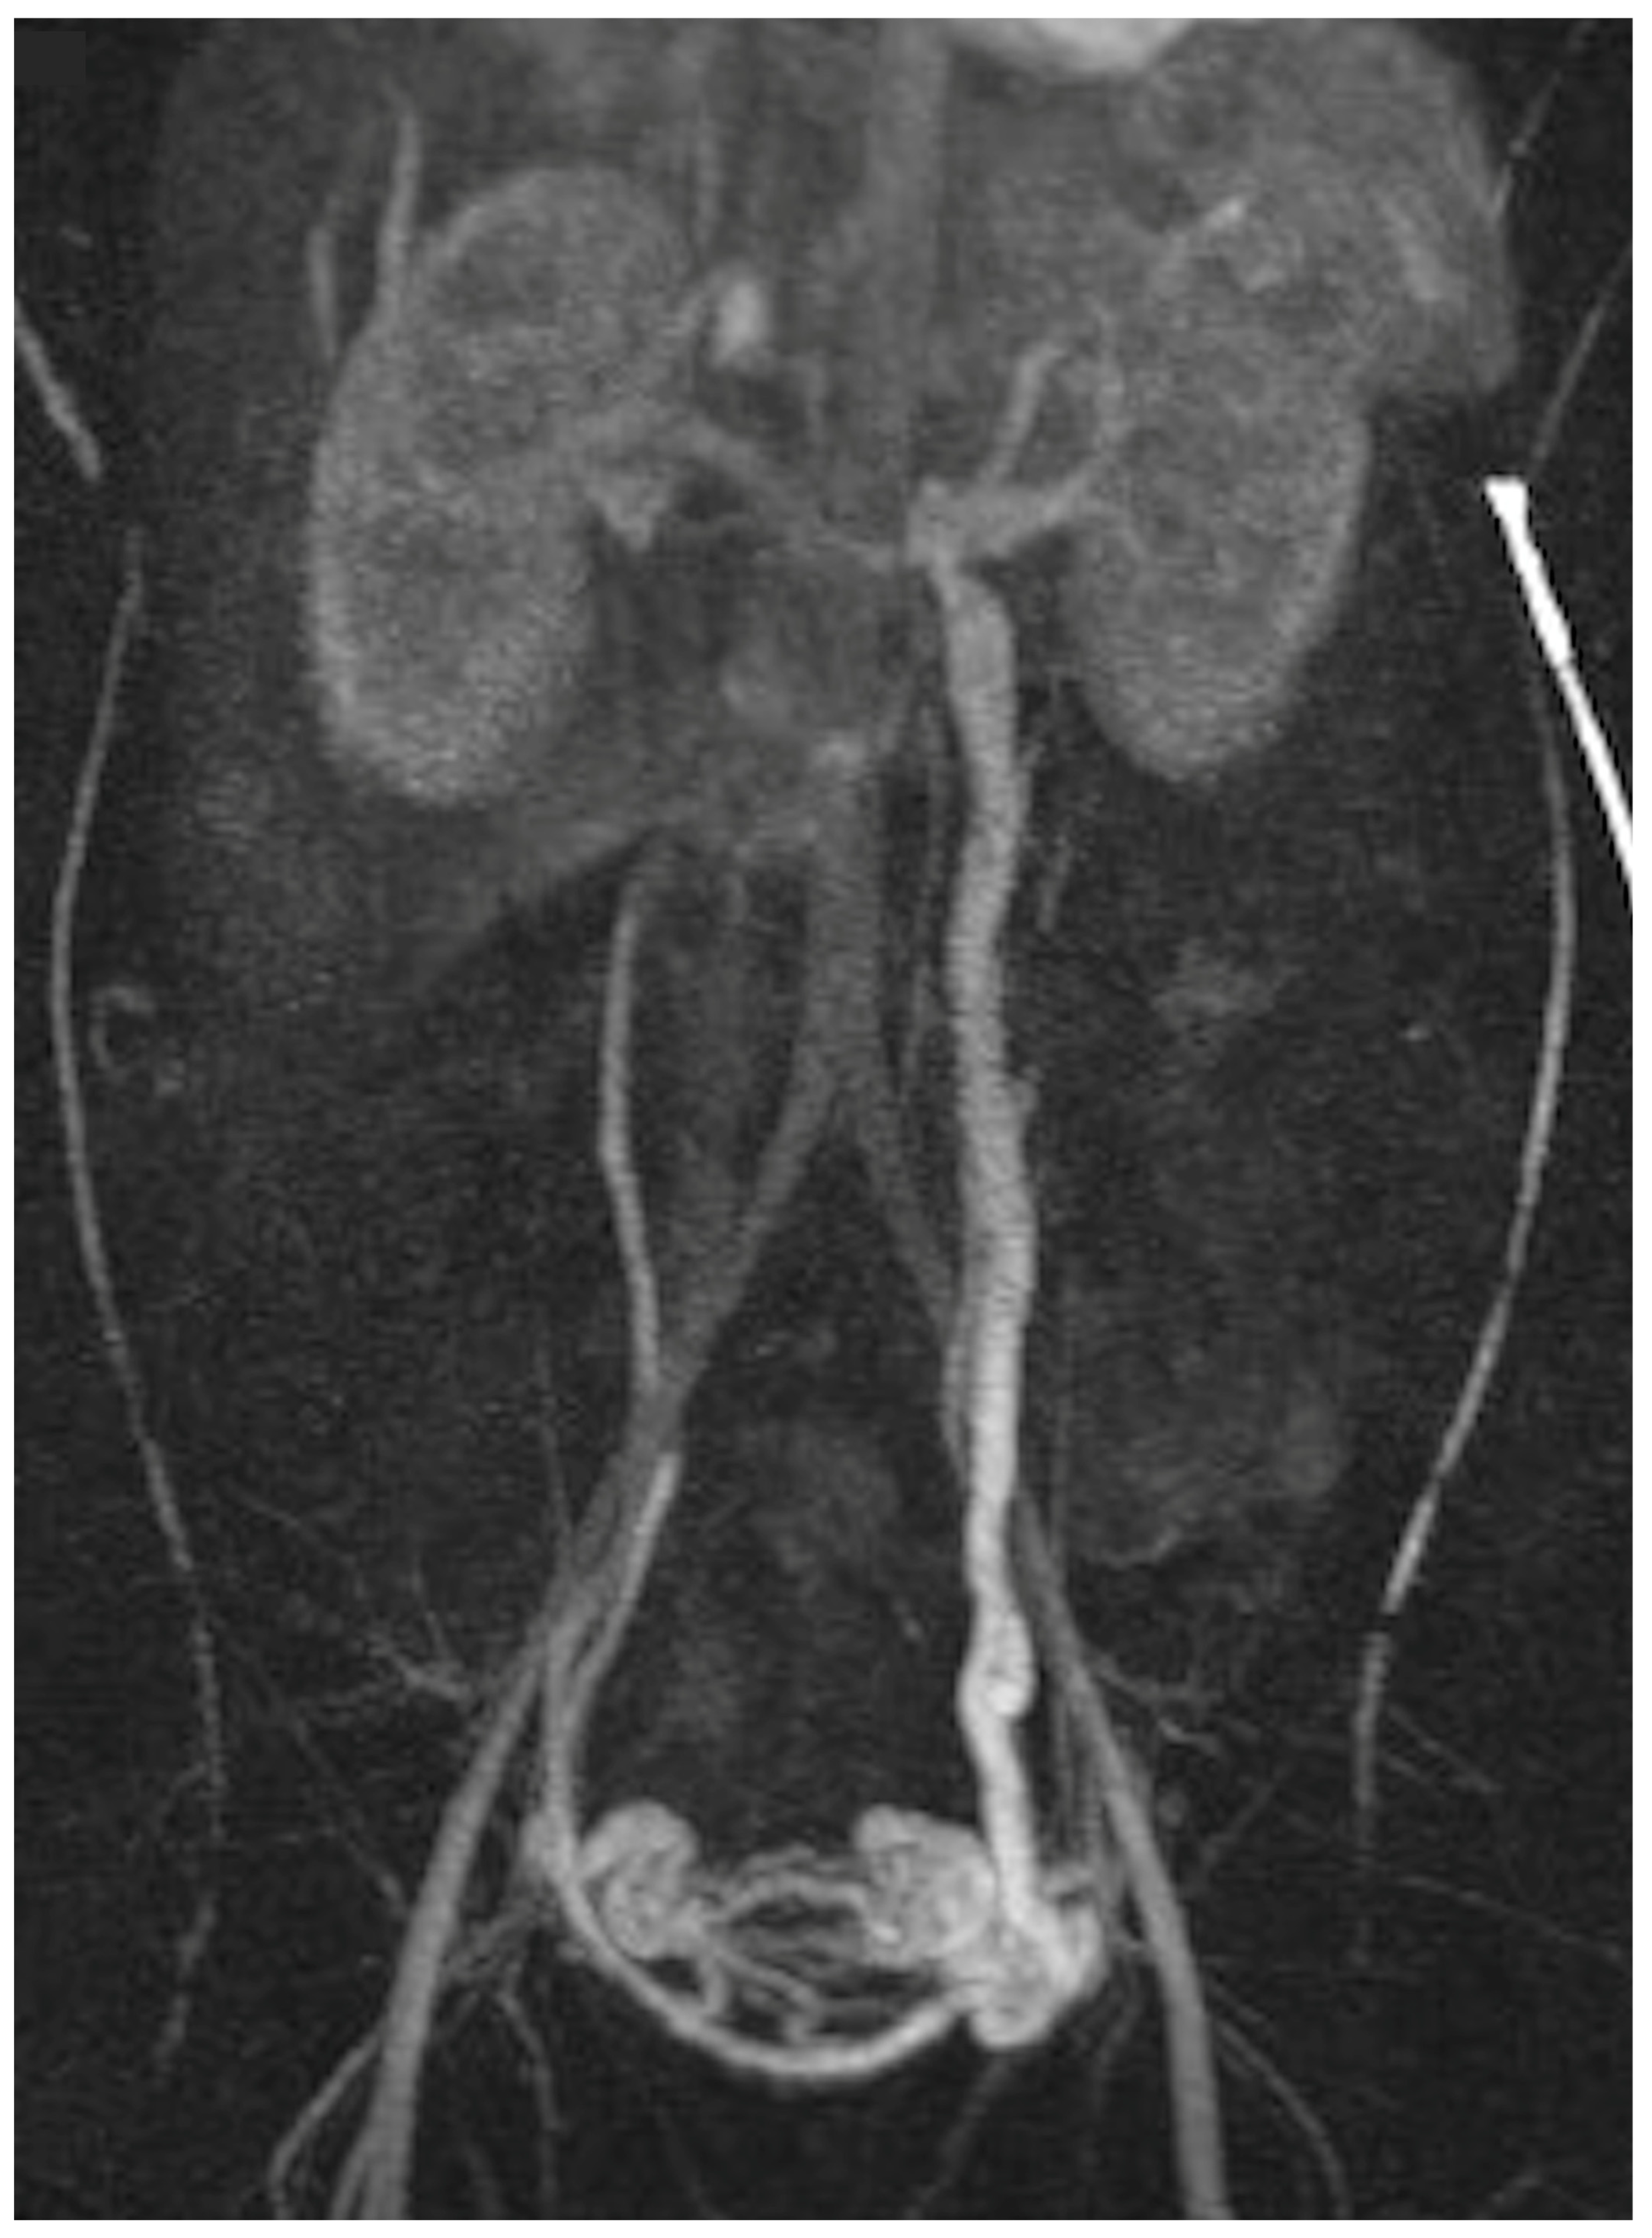

Nutcracker Syndrome as an Uncommon Cause of Isolated Hematuria in Adults

Case Presentation